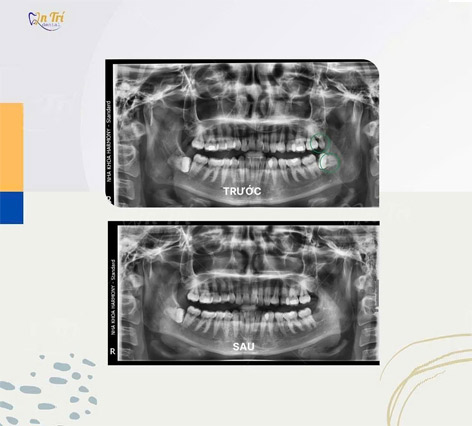

HÌNH ẢNH THỰC TẾ TRƯỚC - SAU ĐIỀU TRỊ NHỔ RĂNG KHÔN

Khách hàng Nguyễn Chí Tài